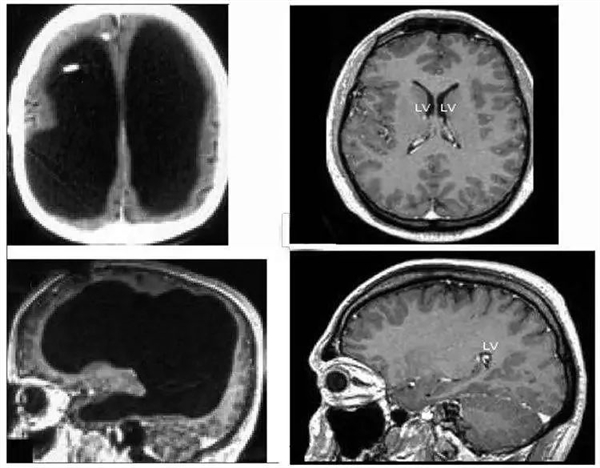

这位患者是法国人,前来就诊时 44 岁,说自己左腿无力已经两星期了。这听起来不是什么严重的大病,但询问病史后医生得知,他在 6 个月时患上了原因不明的脑积水,为此进行了引流,14 岁时又似乎因为引流引发过左腿的运动失调和轻度偏瘫。大概是考虑到旧病复发的可能性,医生对他进行了大脑 CT 和 MRI 扫描。

扫描的结果令所有人大吃一惊。他的大脑中央是一滩巨大的积水,脑子被挤压到了边缘薄薄一层。当然严格来说这也不是纯水,而是脑脊液。正常人脑子内有少量的脑脊液,不断产生又不断排出到循环系统里,保持总量稳定,但这位患者脑内的排水系统发生了障碍,进多出少,导致液体越积越多。

左边为这名法国男子的大脑,中间黑色部分都是脑脊液;右边为正常人的大脑

这个人的脑子被挤压得如此扭曲,所有的脑区都被压扁了,可是不但此前没有症状,还当上了公务员且结婚生子。检查发现他的全量表智商为 75,言语智商为 84,操作智商为 70,虽低于平均值,但也没有低到离谱。